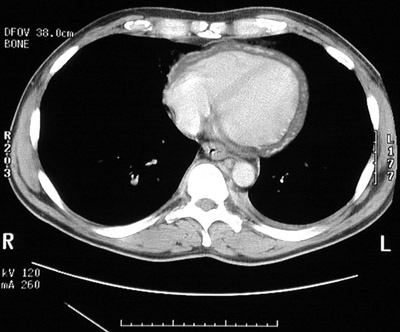

![]() | In this chest CT scan there is a thickened pericardium encasing the heart. Within the thickened pericardium can be seen areas of brighter calcification. This proved to be a tuberculous pericarditis. The thickening and calcification constrict cardiac movement, resulting in a so-called "constrictive pericarditis". |